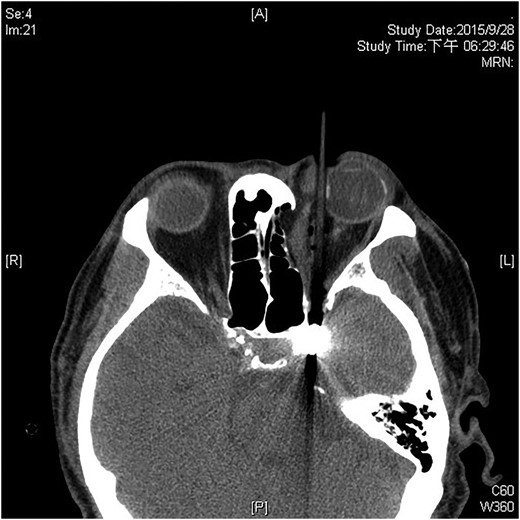

A 60-year-old man was admitted to our medical ward due to aspiration pneumonia. He had a medical history of diabetes mellitus, end-stage renal disease; a tuberculosis bacilli-related thoracic spine infection with paraplegia, and a previous coronary artery bypass graft. During his third day at the hospital, he obtained a ballpoint pen and inserted it into his left eye. On physical examination, the patient appeared to be alert with normal vital signs. The ballpoint pen protruded from his left upper eyelid; it was firmly lodged in his left medial orbit between the globe and nose, causing left eye proptosis (Fig. 1). Neurologic examinations revealed that the patient was neurologically intact except for complete left ophthalmoplegia. Brain CT scanning revealed a tubular foreign body that was located in the anteroposterior plane extending from the orbital apex and directly into the parasellar region (Fig. 2). The metallic portion of the foreign body was entrapped in left optic canal (Fig. 3). There was no evidence of intracranial hemorrhaging or a rupture in the globe (Fig. 4). The patient was treated with high-dose steroids to protect the optic nerve. The plastic ballpoint pen and metallic tip was withdrawn from the orbit smoothly at bedside, and no craniotomy was required. The ballpoint pen had been inserted to an estimated depth of 7 cm through the eyelid and into the orbit. The patient was then transferred to the ICU for close neuro-observation. We initiated intravenous broad-spectrum antimicrobials and vancomycin therapy and continued these medications for three weeks. A psychiatrist was consulted for a complete psychiatric evaluation and suicide prevention. The follow-up CT scan showed no retained foreign bodies or intracranial hemorrhaging (Fig. 5). At the last follow-up examination 2 months after the injury, the patient presented with complete left ophthalmoplegia and blepharoptosis but intact visual function.

The ballpoint pen tip reaches into the parasellar region via the optic canal.